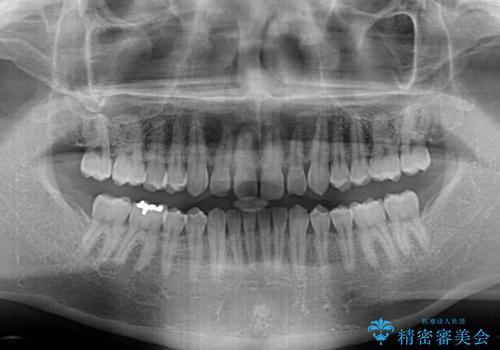

- 前歯の隙間と深い咬み合わせを改善したいとのことで来院された患者様です。

奥歯の咬み合わせは理想的な状態であったため、ワイヤー矯正でもインビザラインでも比較的容易に対応可能でした。